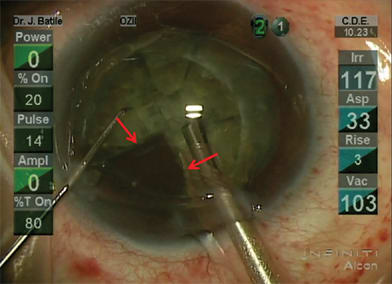

The femtosecond laser enables precise cuts that have important safety and performance implications both peri-operatively and long term. Integrated imaging systems, such as on-board OCT, provide registration to direct the laser both laterally and in depth (Figure 1). For clear corneal incisions, the OCT can provide the corneal thickness at the desired incision location so the architecture for incisions can be properly customized for each patient (Figure 2). This can include the main cataract incision sized for surgical instrumentation, such as the phaco tip and lens injector, and is designed for a watertight seal. It can also include side port incisions. The depth and architecture for relaxing incisions can also be registered, calculated and accurately delivered on the desired axis.

Figure 1. OCT detection of dimensions of anterior chamber and position of anterior and posterior capsule with physician-directed placement of capsulotomy and lens softening-segmentation cuts. Real-time OCT detection of anterior and posterior surfaces of cornea (blue arrows), anterior surface of the lens (red arrows), posterior surface of lens (yellow arrows), planned position and diameter of anterior capsulotomy (white arrows), and the position and depth of the lens segmentation and softening (green arrows).

Finally, the OCT detects the anterior and posterior surfaces of the capsule so customized laser patterns can be delivered to separate the lens (Figure 1). Detection of the posterior surface is critical to maintain a safety zone and prevent laser cuts in the posterior capsule, which could lead to rupture during phaco. The nuclear segmentation can be customized for the lens density to facilitate separation with traditional instruments such as simple spatulas without the need for sculpting or chopping (Figure 5). Additional patterns can soften the lens and match to preferred phaco techniques and lumen size so overall phaco time and energy can be reduced. Patterns can be optimized for followability for phaco dynamics to reduce flow, trampolining, iris prolapse and endothelial cell damage from lens fragments. We have found that quadrant segmentation with a cube-softening pattern can turn a LOCS III grade 4 nucleus into that which resembles irrigation and aspiration needs for a grade 2 nuclear cataract. (Figure 6) There may be added safety benefits with less instrument manipulation from fewer instruments and fewer insertion and removal motions. The integration of advanced imaging technology and customized algorithms with femtosecond laser pulse cutting precision in the cornea, capsule and cataractous crystalline lens provides a new level of safety and security for the cataract surgeon.